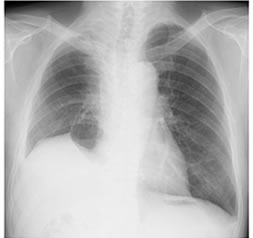

気管支・肺静脈・肺動脈の吻合が終わると、ふたたび血液を流します。自家移植された肺はご自身の肺であり拒絶反応の心配はなく、すぐに機能し始めます。写真は右肺全摘後に右肺下葉の一部(肺底区域)を自家移植された患者さまの3-D CT スキャンとレントゲン写真です。

移植し体内に戻された肺もしっかり機能しているのがわかります。通常2~3週間で退院できます。進行肺癌が対象となっているので、手術後約1ヵ月の時点で術後化学療法を追加いたします。